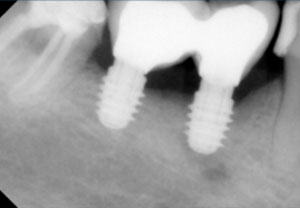

Στις ελάχιστες περιπτώσεις που ένα δόντι δεν μπορεί να σωθεί, δεν θα διστάσουμε να το αντικαταστήσουμε με ένα εμφύτευμα. Η εμφυτευματολογία αποτελεί μια έγκυρη θεραπευτική επιλογή αντικατάστασης δοντιών που δεν σώζονται, με όσο το δυνατό πιο αισθητικό και συντηρητικό τρόπο. Η χειρουργική τοποθέτηση των εμφυτευμάτων πραγματοποιείται από τον εμφυτευματολόγο κ. Μπαρμπετσέα Ανδρέα, ενώ στη συνέχεια η προσθετική αποκατάσταση επί των εμφυτευμάτων , πραγματοποιείται στο ιατρείο μας.